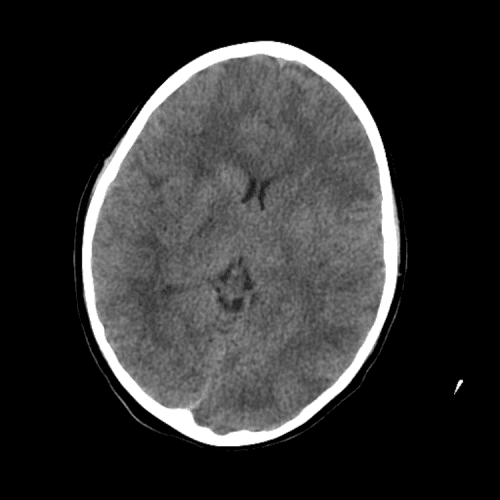

ACA and MCA territory infarct

PCA infarct